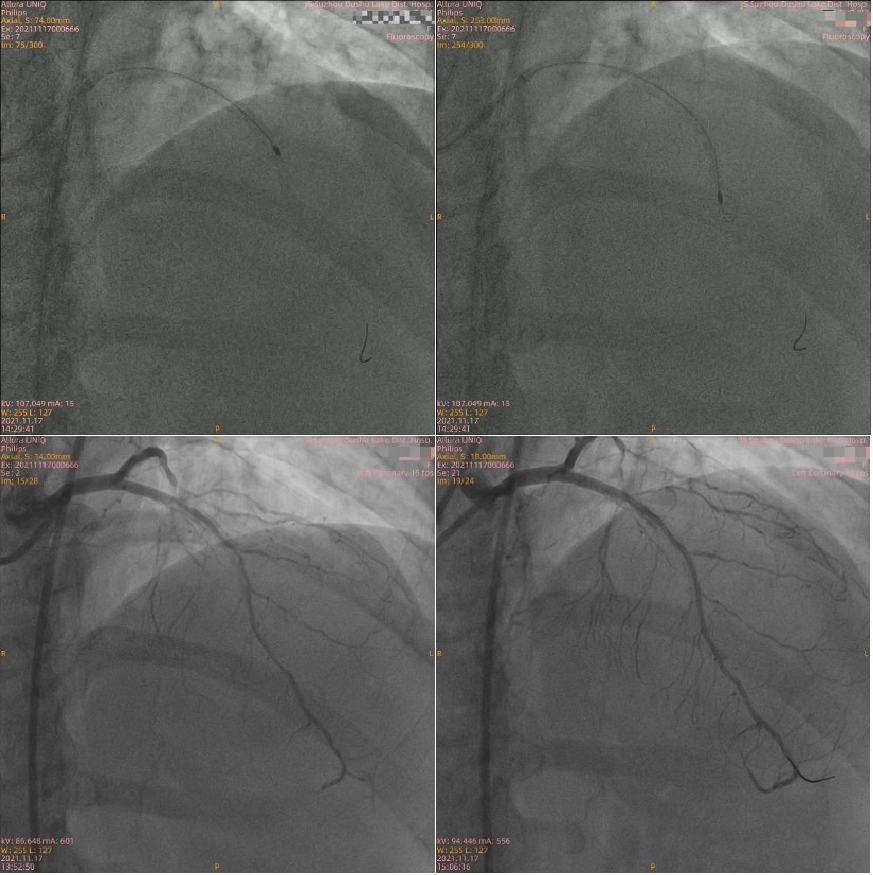

53岁的林女士常感觉活动后胸闷、胸痛,1个月前在当地医院诊断为冠心病,经冠脉造影检查可见冠脉三支病变且伴有严重钙化。当地医生没有尝试介入治疗,建议患者行冠脉搭桥手术。患者及家属考虑到搭桥手术需要开胸,创伤大,思虑再三拒绝了外科手术。转至我院后,找到了周亚峰副院长,周亚峰副院长所带领的介入团队研读冠脉造影影像,制定了血运重建策略:分两步介入。即先为钙化相对较轻的RCA(右冠)及LCX(左旋支)两根血管行介入治疗后,再针对造影所示钙化非常重的LAD(左前降支)行OCT检查,必要时行旋磨治疗。

首次介入手术为第二次介入手术做好血运代偿准备。患者的LCX、RCA血管钙化相对LAD较轻,团队通过国内首个上市的国产切割球囊系统切割钙化病变后让支架顺利植入,这也是该切割球囊系统在江苏省首例应用!

二次介入手术中,团队应用OCT检查血管,血管腔内的结构一览无余。可见LAD管腔内钙化角度大(270°-360°)、钙化非常厚(>1mm)、钙化弥漫(>20mm),钙化评分达到最高分值(CVI:4分),团队决定首选旋磨治疗。LAD应用1.25mm、1.5mm旋磨头以160000转/分的速率高速旋磨,重度狭窄的LAD最终被开通。严重狭窄的血管恢复了畅通,术后林女士胸闷、胸痛症状感到明显好转。